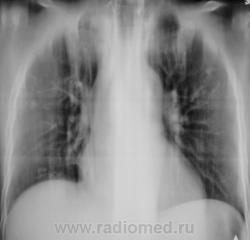

БОМЖ.

Валентин Львович, это тот обещанный случай 3-хдневных "гонений" пациента из обл.туб. к нам.Кстати, как сделать так, чтобы полоски не появлялись при пересъемке фотоаппаратом? Аппарат "Ренекс-Флюоро", 2006 года выпуска.Как на флешку сбрасывать изображения -никто не знает.А завода-изготовителя уже нет.

Контроль через 6 мес.